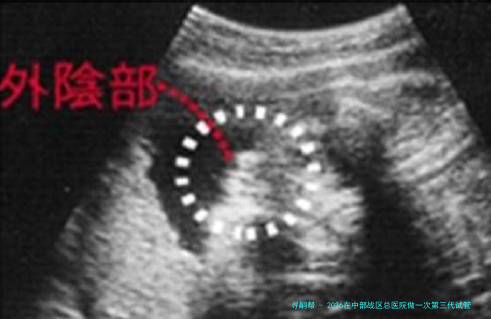

建案与促排卵:拟订方案,进入促排周期,按期监测卵泡发育。

取卵取精与培育:女方取卵同时男方取精,实验室进行受精和胚胎培养。

胚胎活检与筛查:对发育至囊胚期的胚胎进行活检,样品送检验进行遗传课程分数析。